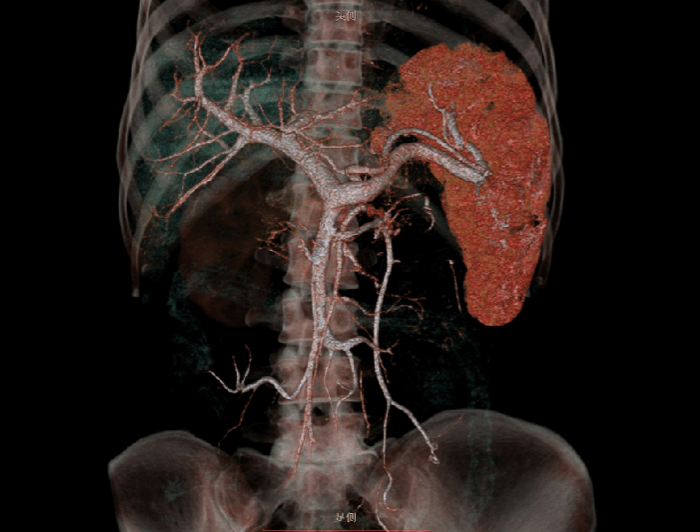

临床应用

高心率:101 bpm

混合斑块

起源异常

头颈CTA

肺结节

肺气肿

主动脉夹层

下肢CTA